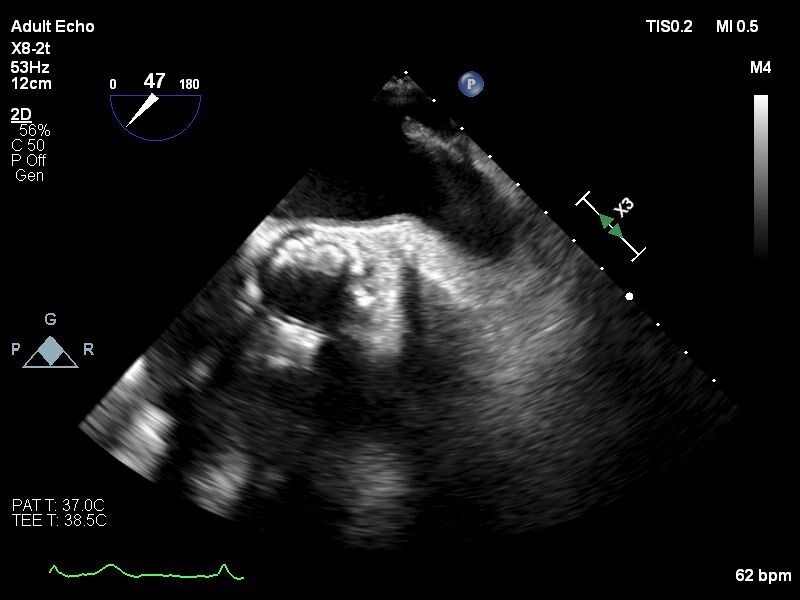

【症例】

80歳代 男性

糖尿病, 高血圧症, 脂質異常症, 持続性心房細動, 食道癌, 胃癌(2020/2), 大腸癌術後(2001,2009), 慢性腎臓病, 高度貧血, TAVI(2019/12 Sapien3 26mm), 冠動脈バイバス術後(2018/04), ラクナ梗塞

しかし出血リスク高く、今回左心耳閉鎖治療予定となる